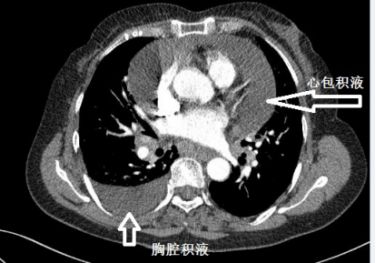

下面这个患者,纵膈淋巴结肿大、融合,心包积液,胸腔积液,一看就是晚期肺癌。后来,纤支镜也确实查到癌细胞。

这个胸水,不好抽,但也不难抽。癌性胸水,不抗癌治疗,不引流,一般不会自行吸收。我带同学去抽胸水,为了安全起见,我事先还是用B超探查了一下胸水,我瞬间就懵了:居然只有极少量的胸水。

复查CT,“癌性胸水”果然无缘无故减少了。

肺癌合并单侧胸水,甚至晚期肺癌合并单侧胸水,不一定是癌性胸水!

这个患者的胸水,应该是心包积液导致静脉回流受阻,体循环淤血引起的。利尿治疗后,胸水减少。

就算是可疑癌性胸水,也要谨慎,之前的影像学检查,要慎重对待!一不小心,就干抽了。